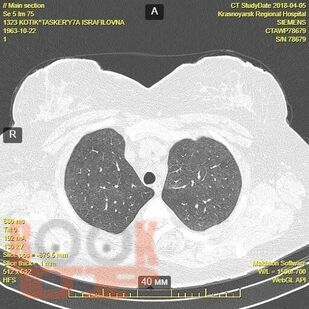

Гранулематозные заболевания легких

Гранулематозные заболевания легких : учебное пособие / И. В. Демко, Н. В. Гордеева, М. Г. Мамаева и др. - Красноярск : КрасГМУ, 2022. - 167 c. - Текст : электронный // ЭБС "Букап" : [сайт]. - URL : https://www.books-up.ru/en/book/granulematoznye-zabolevaniya-legkih-19634258/ (дата обращения: 19.04.2026). - Режим доступа : по подписке.

Учебное пособие предназначено для врачей общей практики, участковых терапевтов, аллергологов, пульмонологов. В настоящем учебном пособии освещены принципы ведения пациентов с диссеминированными заболеваниями легких. Обсуждаются вопросы этиологии, патогенеза, диагностики, а также основные методы лечения.